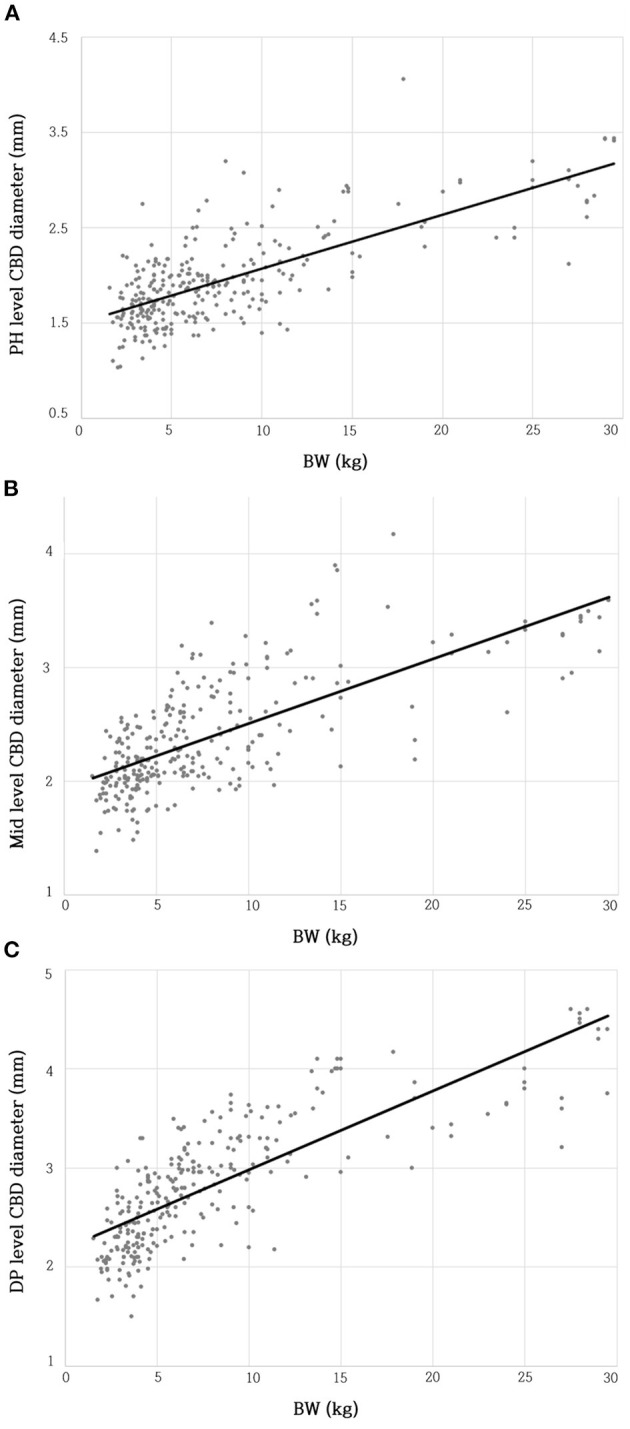

The BW and CBD diameter at the PH level showed a moderate positive linear correlation (R2 = 0.535; β = 0.057; p < 0.001**) (Figure 3A). The BW and CBD diameter at the Mid-level showed a moderate positive linear correlation (R2 = 0.511; β = 0.057; p < 0.001**) (Figure 3B). The BW and CBD diameter at the DP level showed a moderate positive linear correlation (R2 = 0.629; β = 0.079; p < 0.001**) (Figure 3C).